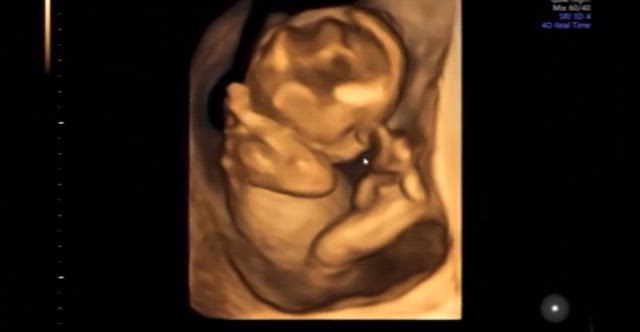

【12w6d】エコーで見えた我が子の癖(動画有)